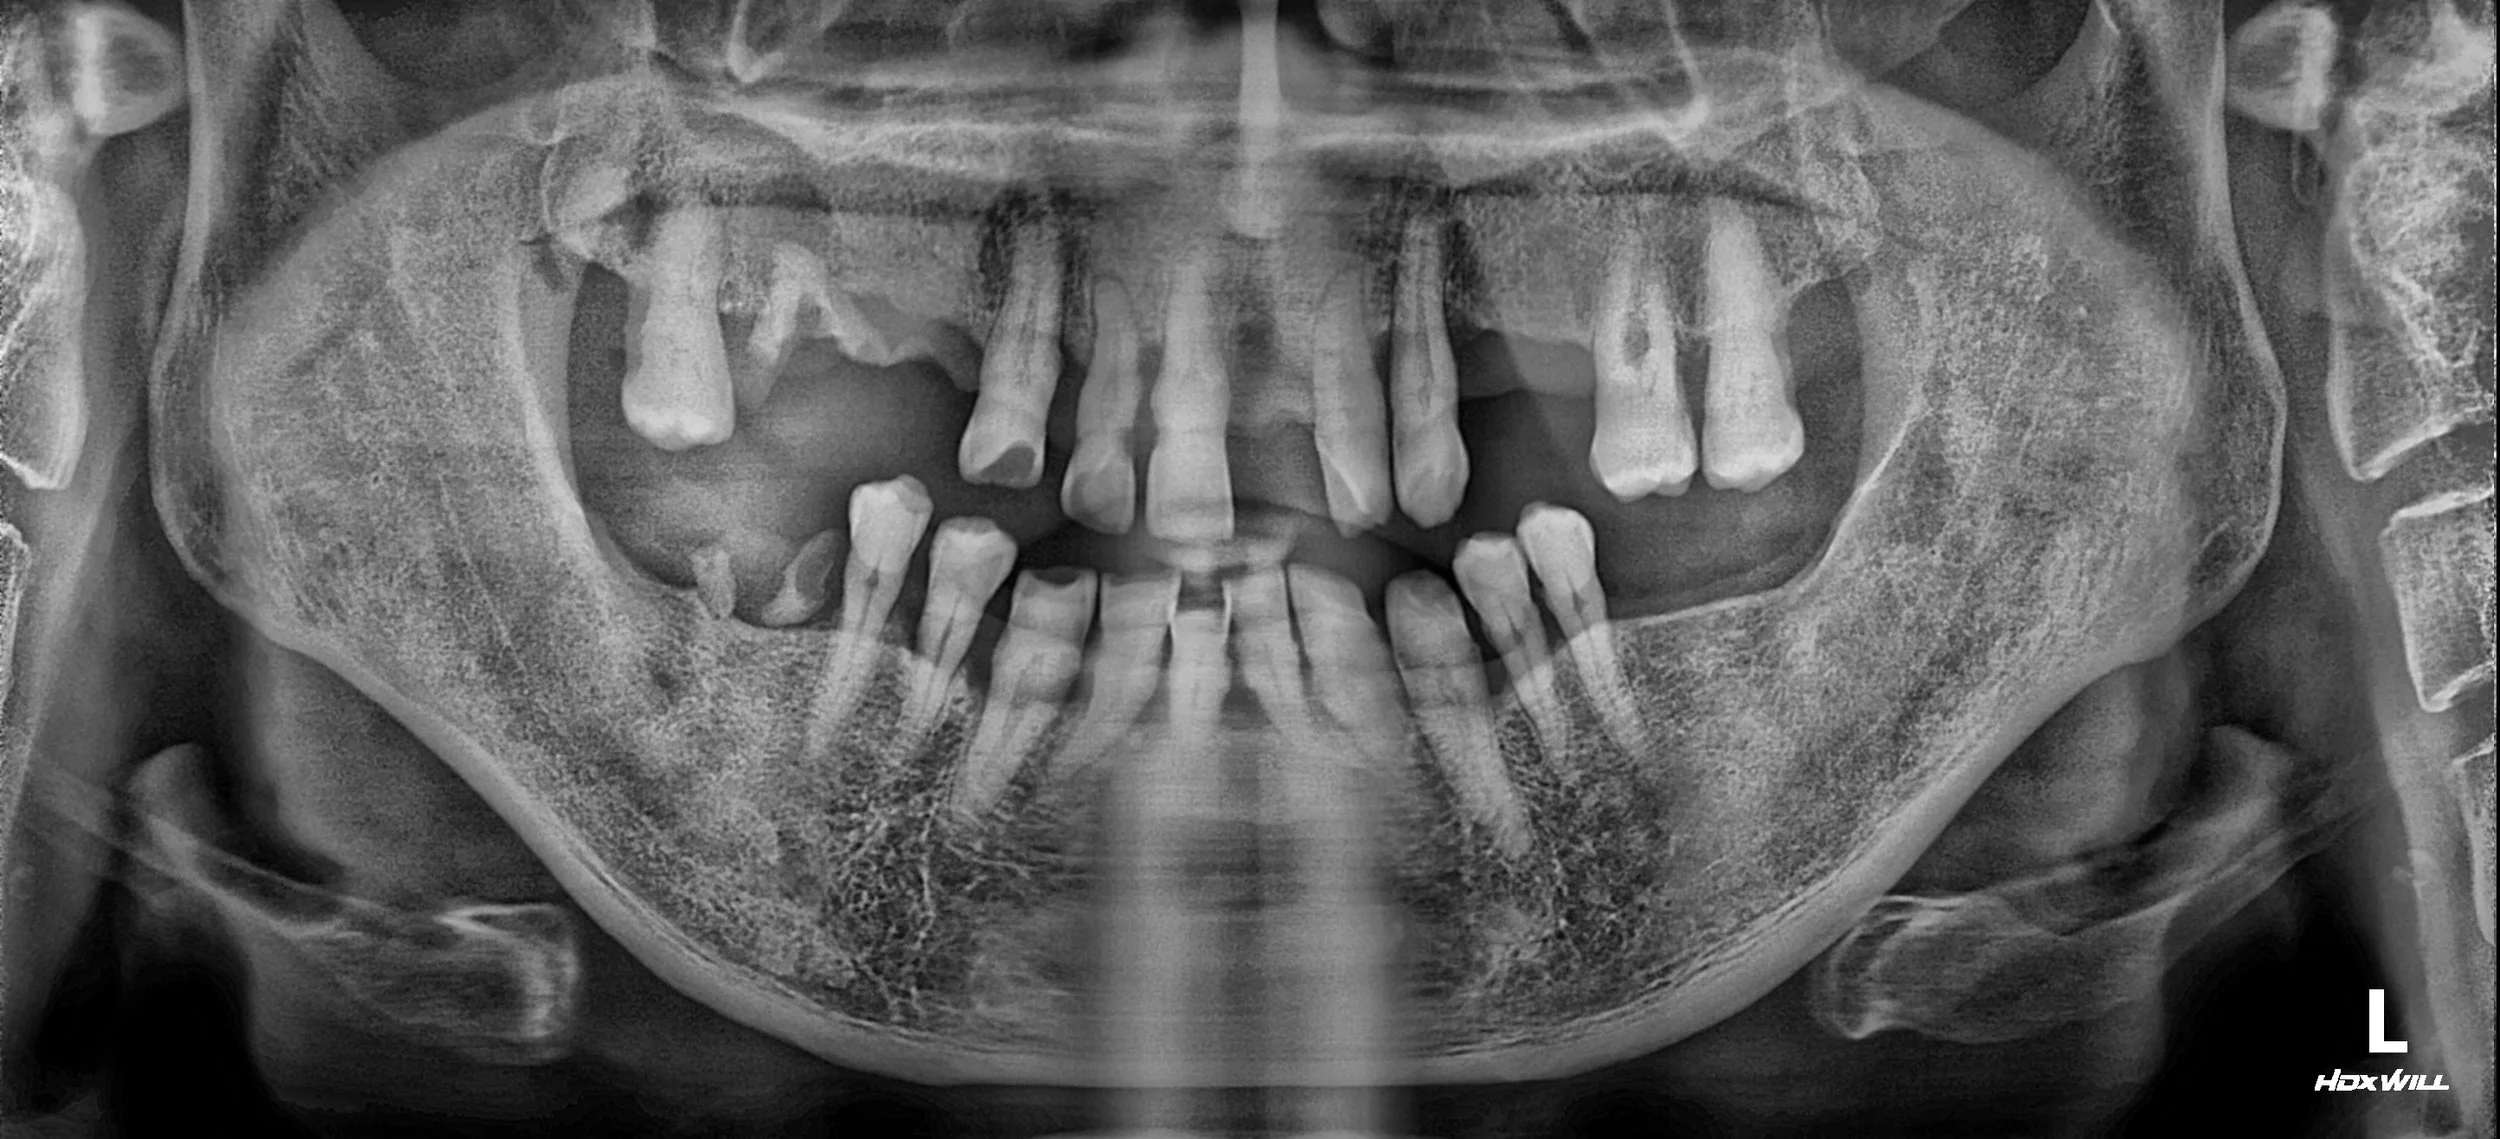

Contact

35. Comprehensive Full-Arch Transformation: Restoring Confidence in a Young Phobic Patient

Reversing the effects of generalized rampant caries and occlusal collapse in a female patient in her 20s. A tooth-preserving, implant-assisted approach focused on stable VDO elevation and overcoming social anxiety.